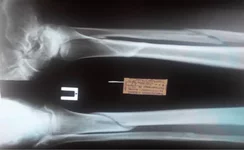

̶С̶а̶п̶,̶ ̶м̶е̶д̶а̶ч̶.̶ ̶Е̶с̶т̶ь̶ ̶о̶д̶н̶а̶ ̶н̶о̶г̶а̶.̶ ̶ Доброго времени суток. мне 25лет, рост 177, вес 65. Почти пол года назад (2.02.14) сломал ногу, получил винтообразный перелом н/3 большеберцовой и с/3 малоберцовой костей.

Консолидация протекала медленно, и вот, ура. Врач сказал, что освобождает меня от гипса 19.17.2014. Мол нога срослась и могу ходить, месяц на костылях приступая и распределяя нагрузку по +30% в неделюю.

смутила меня врач-рентгенолог, которая когда делала описание, отругала меня за то, что я операцию не делал и вроде как рано снял повязку, мол там еще срастается. Еще в описание добавила развитие посттравматического деформирующего артроза голеностопного сустава. Я как прочел в интернете, что такое артроз, так и офигел от такого приговора на всю жизнь. При том, что травматолог и словом не обмолвился по поводу артроза.

прилагаю последние снимочки. призываю товарищей-докторов в этот топик:молись:.